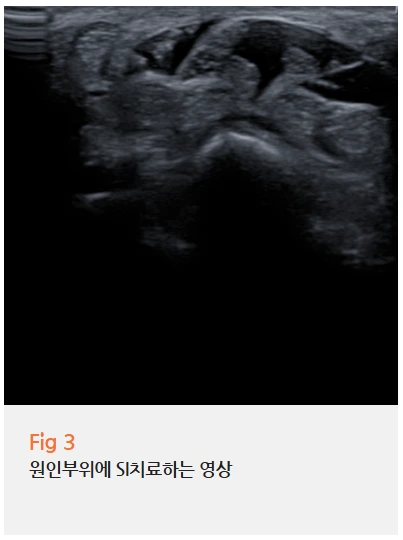

환자분께는 SI (초음파 유도하) 주사치료를 시행했어요.

초음파로 정확한 위치를 보면서,

염증이 생긴 인대 주변에 직접 약물을 주입하는 거예요.

맹목적으로 찌르는 게 아니라,

실시간으로 바늘 끝이 어디로 가는지 확인하면서 주사하기 때문에 정확도가 훨씬 높아요.